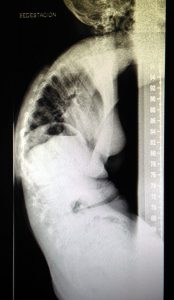

Radiografia lateral sense Spex

Com es pot apreciar en aquesta radiografia, aquesta nena presenta cifosi, una curvatura fisiològica de la columna vertebral a la regió dorsal, així com retroversió de maluc.